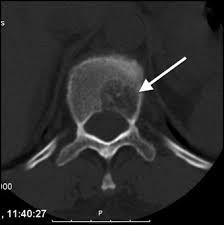

The tests were repeated for the patient again, general and comprehensive blood tests were performed and all agreed to a high levels of adrenal hormones in blood , radiographic images were also done in addition to magnetic resonance images throughout the body, the result of the tests and imaging was for the brain CT scan showed that there was no focal brain lesion and it was a metastatic spread test only, and no shift of midline structure and normal ventricular system, as the lumber spine CT showed that the findings were evidence of multiple bony lytic lesions seen in the lumber spine and sacral bone and no evidence of disc herniation or nerve root compression as showed in figure (7 ), this all tells that all back pains suffered by the patient were due to the presence of the tumor only .

The pelvic MRI showed that there were multiple hyper intense signals seen in the left ischium, that suggested bone metastasis while the abdominal MRI showed that there were a 6.75.3 cm right a adrenal mass lesion which appears isointense with thick wall moreover the neck Ultra sound showed a (97*11 ) mm nodule in the lift lobe with spots of calcification in the thyroid gland enlarged and indicating thyroiditis, after all of those critical signs shown through the previous medical scans , PET-CT scan was advised to insure the presence and the location of the primary lesions and the metasticitc spread , and after undergoing a PET-Ct scan the result showed a hypermetabolic and mostly malignant right adrenal mass with bone metastasis .

For Pet-Ct images taken for the patient pre and after the chemotherapy which shows no significant changes in the tumor distribution or size after chemotherapy.

nificant difference from the previous scan in 2004. (16- Jordanian medical services, PACS system and database store center).